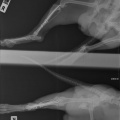

Koer on opereeritud.

Tagumise käpa luumurd.

Koerake sattus varjupaika vigastatud käpaga. Ülevaatusel selgus, et koera käpal on mitmekordne luumurd. Pidime paigaldama ka kateetri, kuna ta ei saanud pissida (ilmselt autolöögist põhjustatud kusepõie atoonia).

Собака поступила в приют с множественным переломом ноги. Не могла пописать (видимо был удар машины и, как результат, атония мочевого пузыря). Нога в очень тяжёлом состоянии, и завтра мы кладём собаку на операционный стол.